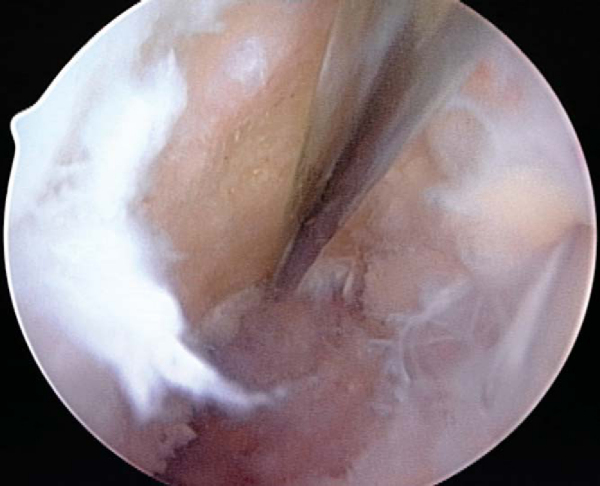

3. Notch Preparation and Notchplasty

While the graft is being prepared on the back table, the intercondylar notch is prepared and notchplasty may be performed as needed. The ACL stump as well as residual soft tissue is removed from the lateral wall of the notch and the tibial footprint by arthroscopic instruments, the shaver, and electrocautery. A curet can also be a helpful and efficient tool to remove residual soft tissue from the posterior aspect of the lateral wall. Fat pad and ligamentum mucosum are removed as needed to improve visualization. Once all remaining soft tissue is removed from the notch, a notchplasty is performed if needed to avoid graft impingement, particularly in full knee extension (

Fig. 60-5

).

A notchplasty can also be necessary to improve visualization of the “over-the-top” position on the femur. A ¼-inch curved osteotome, placed through the inferomedial portal, is used to begin the notchplasty on the articular surface, and the arthroscopic grasper is used to remove the fragments. Next, with a 5.5-mm spherical bur, the notch is widened from posterior to anterior and apex to inferior. Commonly, a vertical ridge is present approximately 1 cm anterior to the posterior edge, which can be misidentified as the posterior wall (“resident’s ridge”). A probe must be able to hook under the over-the-top position, and it is used to confirm the sharp edge signifying the correct posterior aspect of the notch (

Fig. 60-6

). It is important to avoid excessive removal of bone along the lateral femoral condyle to prevent excessive lateralization of the isometric point.